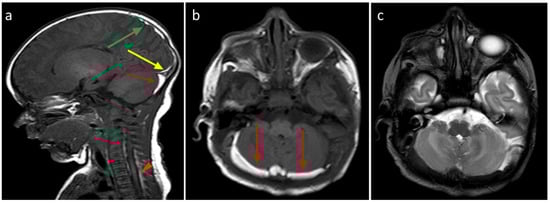

Figure 4. (a) Birth-related SDH in a 2-day-old infant born spontaneously. Right paramedian sagittal plane SE T1-weighted sequence—panoramic view of multiple subdural hematomas showing occipital supratentorial (yellow arrow) and parietal (green arrow) and cerebellar infratentorial (red arrow) distribution but also in the spinal canal anteriorly and posteriorly in the cervico-dorsal tract (arrowheads). (b) Axial T1-weighted SE sequence passing through the posterior cranial fossa—the infratentorial hematoma shows a development posterior to the vermis and the cerebellar hemispheres, with a greater thickness on the right (arrows). (c) FSE T2-weighted sequence on the axial plane at the same level as (b) (b)—the hematoma shows a hypointense signal, less easily appreciable (arrows), but which, in relation to the hyperintense appearance in T1, allows us to date the hematoma.

Figure 5. In the same patient in Figure 3, birth-related SDH in an 11-day-old infant born spontaneously:a Axial SE T1-weighted sequence at the level of the basal ganglia—subdural hematoma with occipital and temporal distribution (arrow). (b) FLAIR T2-weighted sequence on the axial plane at the same level as in Figure 4a.The hematoma appears hypointense (arrow) and, considering the hyperintensity on T1, it can be dated as early subacute (intracellular methemoglobin). (c) SE T1-weighted sequence on the axial plane passing through the distal cervical tract confirms (arrowhead) what was described in Figure 4a.